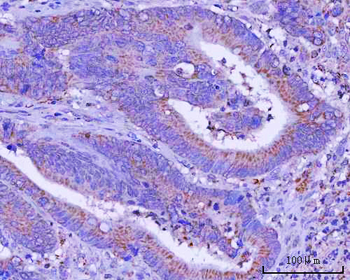

IHC staining of FFPE human lymph node with CD72 antibody (clone BU40). HIER: boil tissue sections in pH9 10mM Tris with 1mM EDTA for 20 min and allow to cool before testing.

IHC staining of FFPE human lymph node with CD72 antibody (clone BU40). HIER: boil tissue sections in pH9 10mM Tris with 1mM EDTA for 20 min and allow to cool before testing.